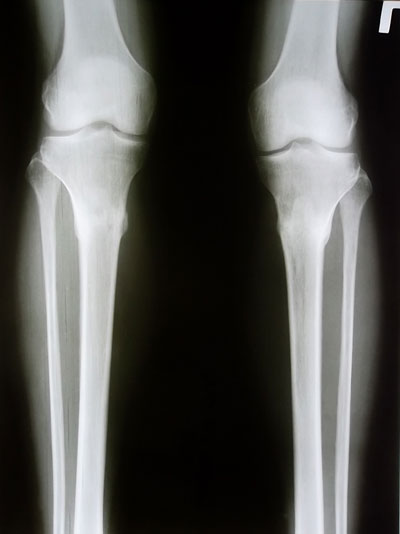

7 месяцев с момента операции и 3,5 месяца после снятия аппаратов.

Рентгеновские снимки через 3,5 месяца после снятия аппаратов.

Регенерат мощнейший, никаких ограничений нет, каблуки любой величины разрешили.